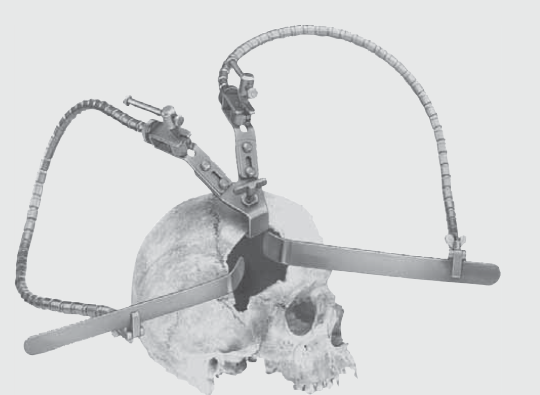

FF262R ~ HIRNSPATELHALTER YASARGIL DOPP.END. ~

selbsthaltender Hirnspatelhalter nach YASARGIL, doppelendig

bestehend aus:

FF268R Grundkörper zur Aufnahme von zwei flexiblen Armen

FF270R 2 flexible Arme

FF273R 2 Halter für flache Hirnspatel